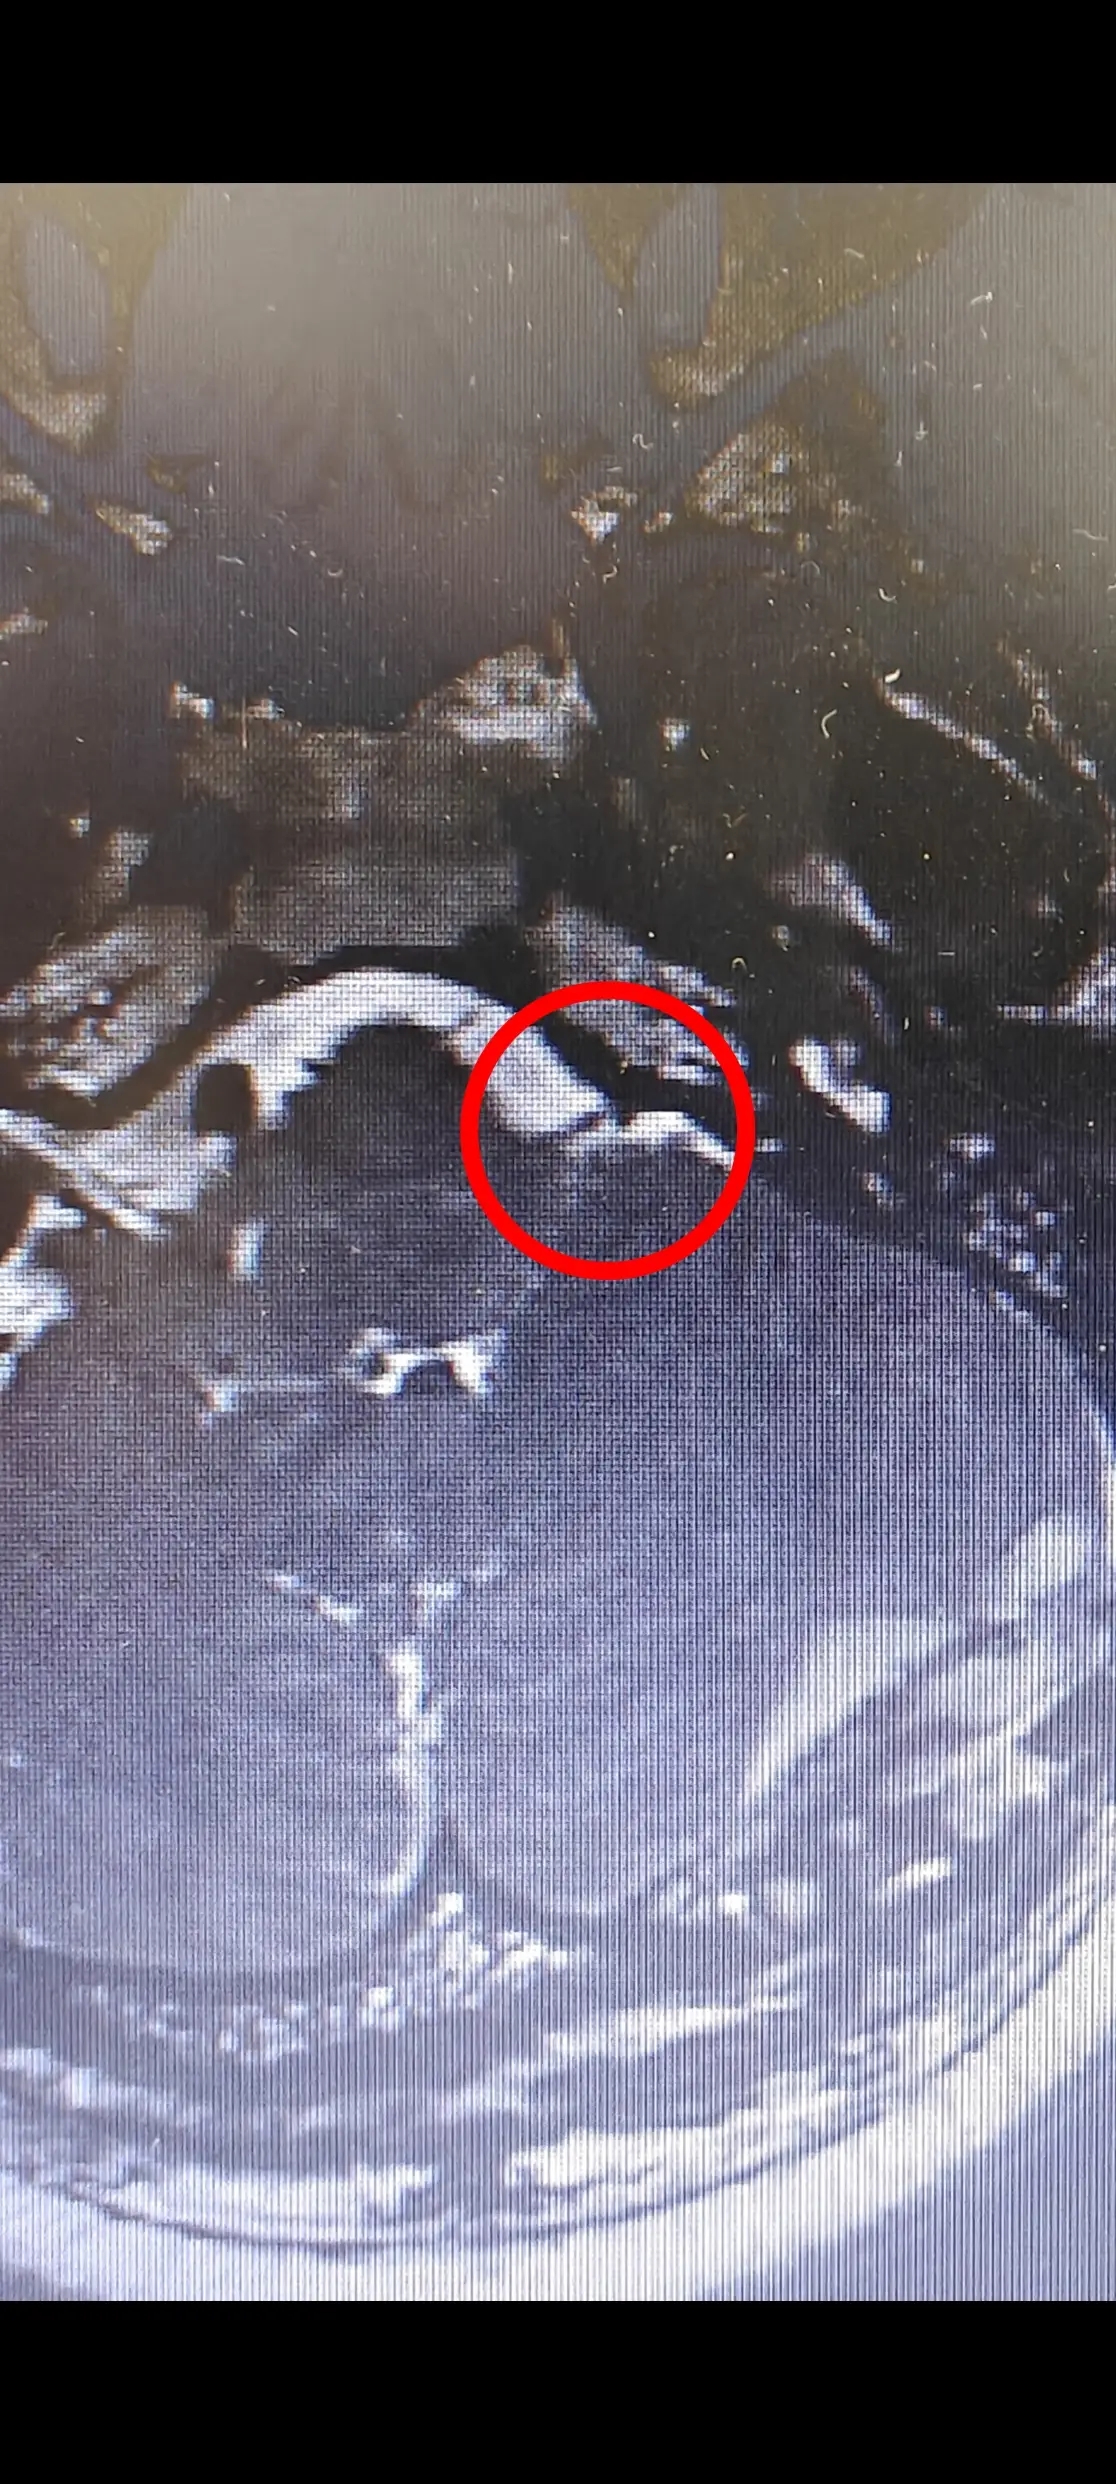

苑玉清主任从事神经外科工作已有 30 余年,结合张阿姨之前的检查报告,经过详细问诊后,苑主任敏锐地判断张阿姨是「听神经压迫」导致的颅鸣而不是简单的耳鸣。为了确诊病情,医院为张阿姨做了影像学检查,头颅 MRI 显示张阿姨确实是左听神经受压。